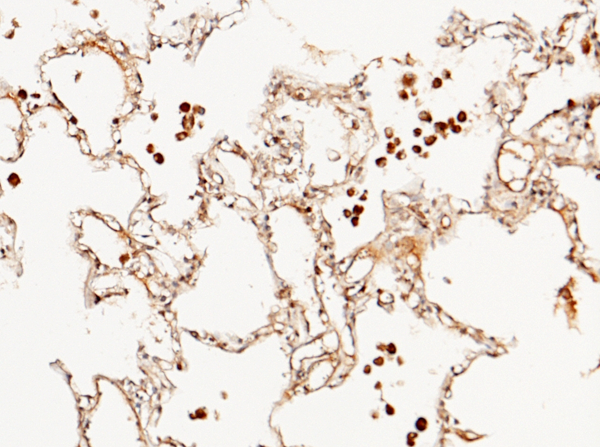

(Immunochemical staining of human FLRT3 in human lung with rabbit polyclonal antibody (1:1000, formalin-fixed paraffin embedded sections).)